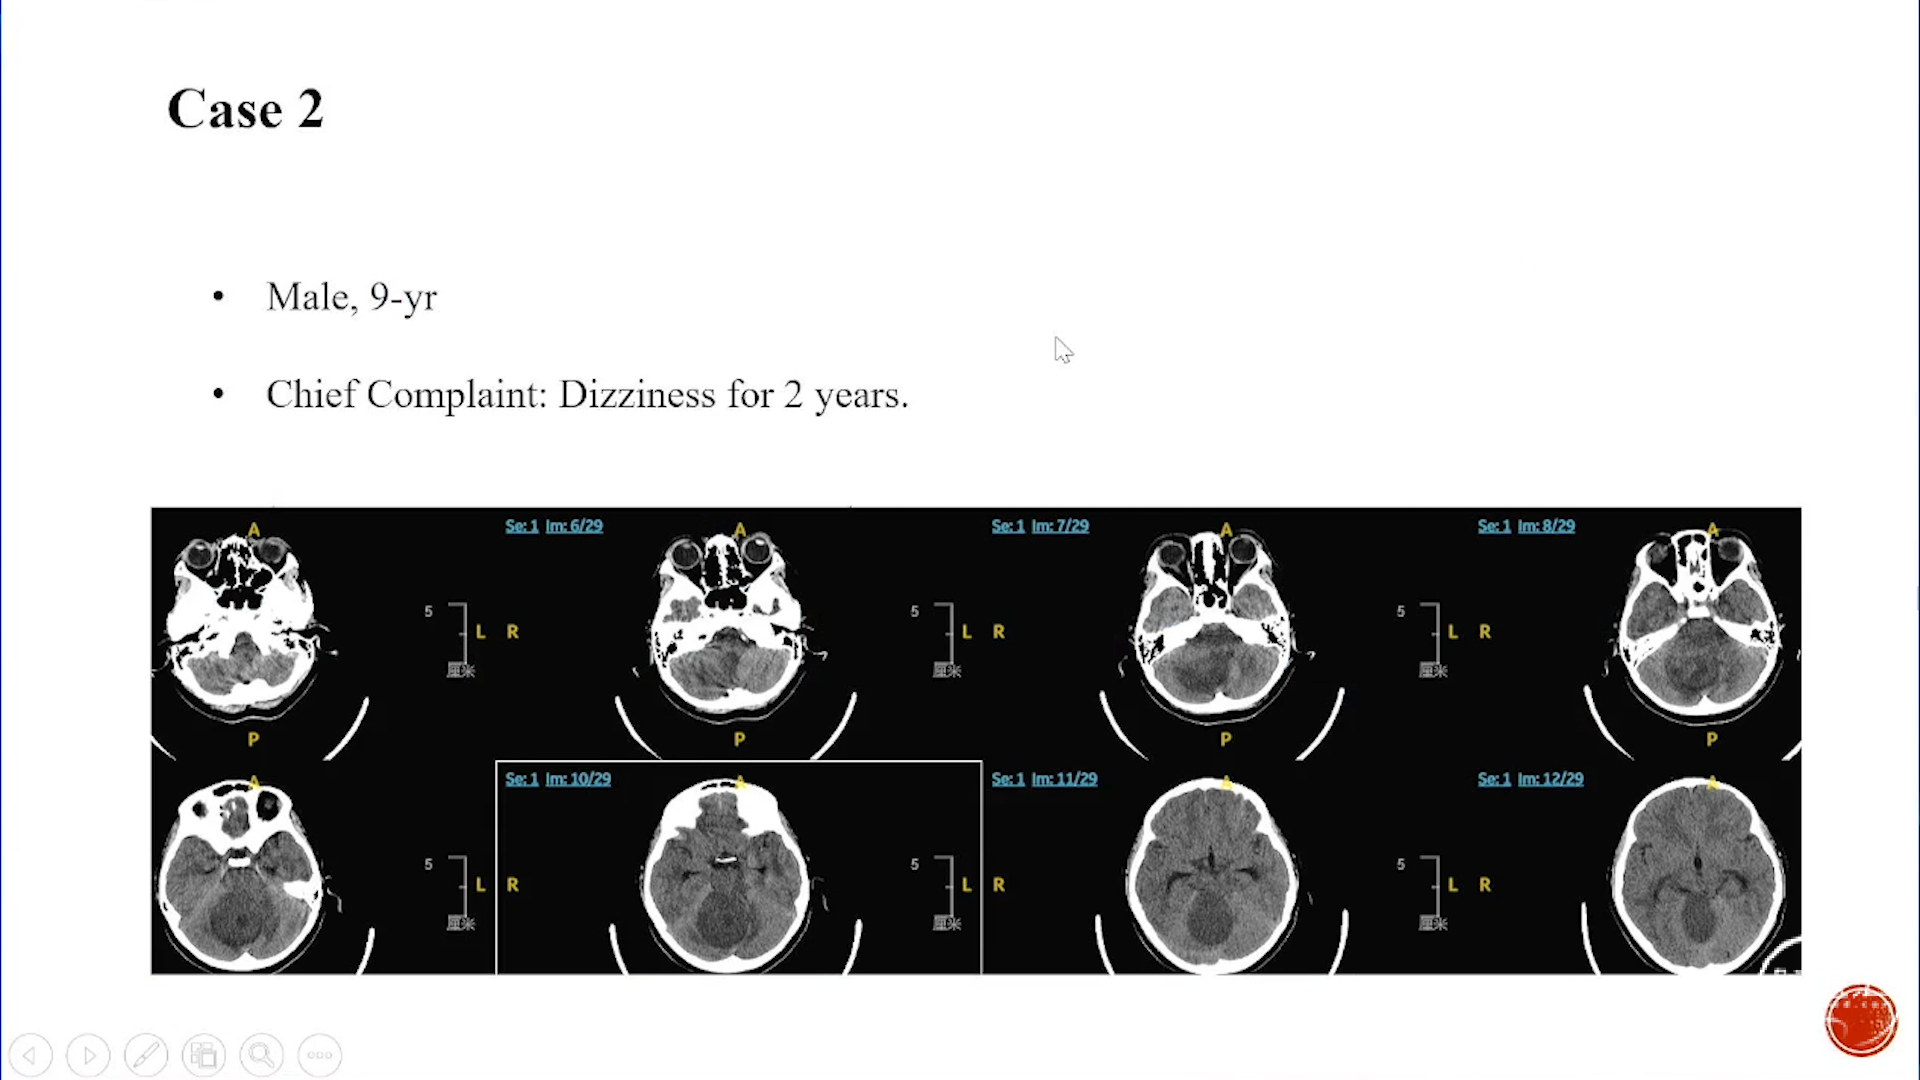

小脑星形细胞肿瘤